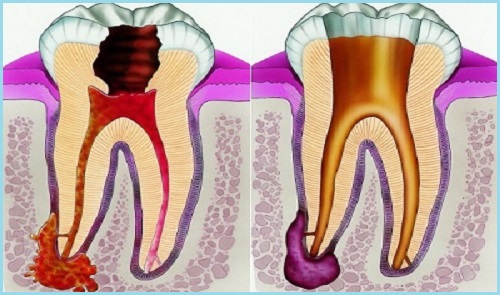

Пульпит - воспаление мягкой ткани (пульпы), которая состоит из нервов, кровеносных сосоудов и соединительной ткани. Восполительный процесс протекает в пульпарной камере и корневом канале зуба.

Пульпит бывает: острый и хронический.

Для острого пульпита характерны самопроизвольные, приступообразные боли, которые усиливаются ночью.

При хронических пульпитах боль не всегда острая, резкая но всегда напоминает о себе при действии внешних раздражителей на зуб.